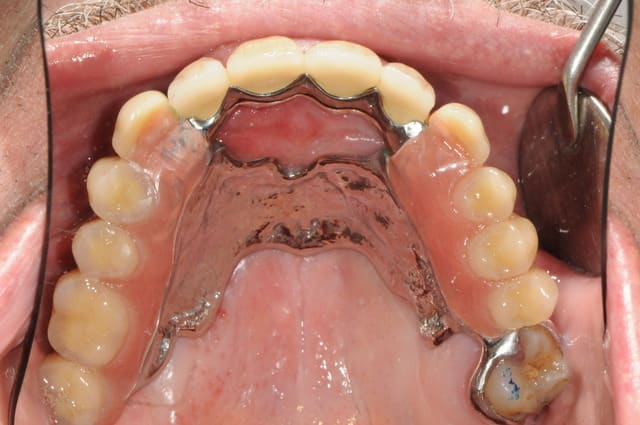

si ça peux alimenter ta réflexion...

manque d'intelligence de ma part j'ai pas fait de photo du cas au tout départ. mais la première photo devrait vous donner une idée du reste...

la suite c'est pose 4 implants, ceramique, stellite sur locators (beaucoup moins couteux qu'une barre et plus facile à nettoyer)

Sur la photo "5658", il y a rougeur importante sur la

crête/gencive. Je crois que ton occlusion est trop forte. Dommage qu'il manque un appui plus postérieur dans ce coin.

> Sur la photo "5658", il y a rougeur importante sur la

> crête/gencive. Je crois que ton occlusion est trop forte.

mais non, c'est une photo avant juste avant la pose du nouvel appareil. ici, la gencive est un peu traumatisée par le vieux partiel résine qui servait de cache misère.

Dommage qu'il manque

> un appui plus postérieur dans ce coin.

> L'ensemble st quand même très bien.

j'aurai bien voulu, mais cela aurit demandé un sinus lift (non accepté par le patient)

en fait le boulot n'est pas complétement terminé car après les implants sur 35/36 qui sont ici visibles je doit corriger la courbe occlusale en m'occupant de 43à46